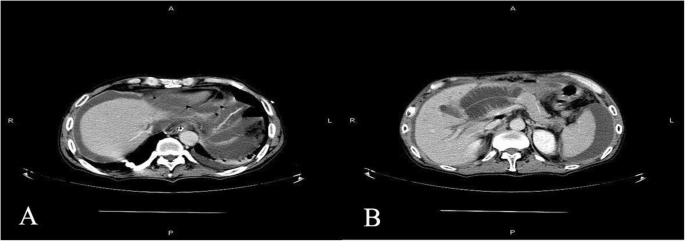

On postoperative day (POD) 1, the endotracheal intubation was removed and gastrointestinal function was restored. A liquid diet was then given on POD 5 and a semi-liquid diet was given on POD 7. During this process, the vital signs and drainage amylase test results of the patient were normal. On POD 9, the patient suddenly experienced severe epigastric pain accompanied by nausea and vomiting. Physical examination revealed tension in the abdominal muscles, tenderness throughout the abdomen, and rebound pain. The patient’s heart rate was 130 beats/minute, blood pressure (BP) was 106/67 mmHg, leucocyte count was 8.25 × 109 cells/L, and drainage amylase level was 21.8 U/L. Emergency total abdominal computed tomography (CT) showed a small amount of fluid in the abdominal and pelvic cavities, a dilated bowel, and effusion in the upper abdominal bowel cavity, which was considered to be an obstruction. The patient was admitted to the intensive care unit and received conservative treatment, including fasting, gastrointestinal decompression, anti-infective treatment, proton pump inhibitors, somatostatin, and analgesia. On POD 10, the heart rate was 170 beats/minute, BP was 108/59 mmHg, leucocyte count was 13.15 × 109 cells/L, and drainage amylase level was 145.5 U/L. Reexamination using total abdominal CT suggested bilateral subdiaphragmatic free gas, abdominal and pelvic effusion, anastomotic leakage (Fig. 3a), expansion of the upper abdominal bowel, effusion, and obstruction (Fig. 3b). Subsequently, the patient appeared to be unconscious, and he was given assisted breathing by endotracheal intubation ventilation, continuous renal replacement therapy (CRRT), and peritoneal puncture and drainage under ultrasound guidance. About 1000 ml of yellow-green fluid was extracted, and the level of amylase in the drainage fluid was 896.3 U/L.